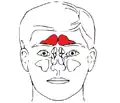

Seios frontais (em vermelho).

Seios frontais (em vermelho). -